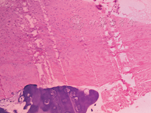

左侧股骨远端病灶活检术:术中见左侧股骨远端病灶处骨膜与骨皮质黏连,骨皮质变薄、表面粗糙,骨腔内病灶组织似玻璃软骨样组织。病理诊断:(左股骨远端)软骨瘤(图4)。出院诊断:双侧肱骨头、双侧髌骨、双侧股骨下端干骺端、双侧胫腓骨上端干骺端多发性软骨瘤。

诊断该病首选X线片,典型特点为骨干呈囊状膨胀或干骺端膨胀增宽,内有多发小囊状及柱状低密度区,其内可见斑点状、条索状或不规则钙化[8],若诊断困难,可进一步行CT检查,更能清楚显示瘤体内钙化。但病变初期影像学检查无特异性,易误诊。典型病理特点为瘤体内软骨细胞分隔成小叶状,细胞量较少,软骨细胞排列整齐,并见大量软骨基质[9]。本例患儿行X线片、CT、ECT检查均未提示内生性软骨瘤可能,影像学检查缺乏特异性,且该患儿仅有局部疼痛的临床表现及病变呈对称性分布,易误诊,故初步考虑内科疾病或恶性肿瘤骨转移可能,后行病灶活检病理诊断软骨瘤。